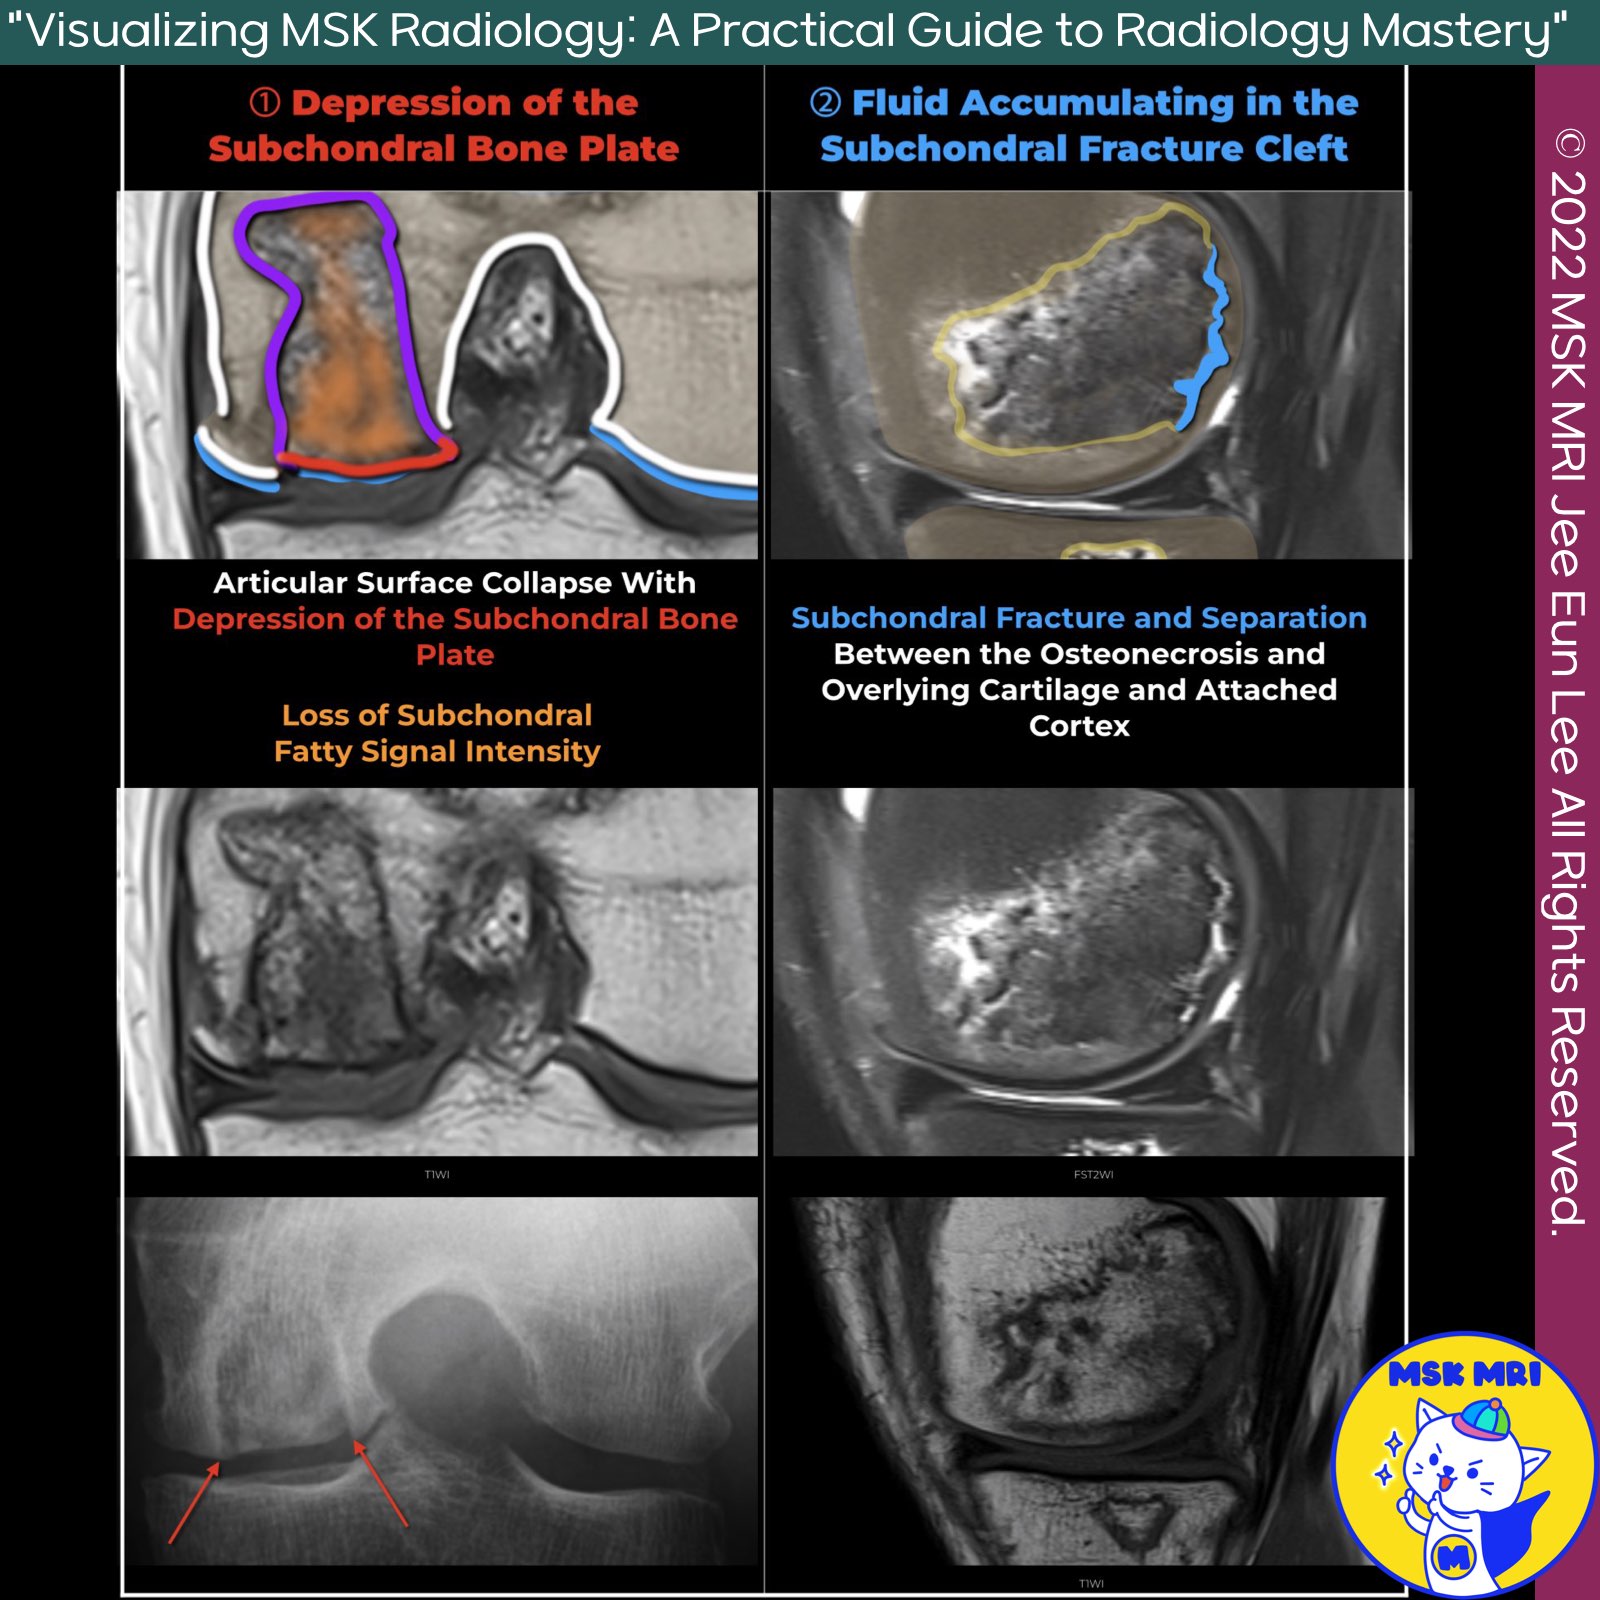

📌 Fracture of the Subchondral Bone Plate in Osteonecrosis

✅ Epiphyseal Collapse

- Epiphyseal collapse in osteonecrosis is characterized by a deformity of the subchondral bone or a fluid-filled cleft, or both.

- This condition is better visualized on radiographs or CT images, likely due to the higher spatial resolution they provide

✅ MRI Patterns of Subchondral Bone Plate Fracture

The fracture of the subchondral bone plate can present two patterns on MRI:

- Depression of the subchondral bone plate: This pattern shows a loss of epiphyseal contour

- High-signal-intensity line on T2-weighted MR images: More rarely seen in the knee, this pattern represents fluid accumulating in the subchondral fracture cleft, extending under the subchondral bone plate

✅ Changes in Signal After Articular Collapse

- Following articular collapse, the signal in the necrotic segment changes due to fragmentation, invasion of fibrovascular tissue, and secondary cyst formation.

- The normal fatty signal intensity on T1-weighted images is lost, replaced with inhomogeneous low to intermediate signal intensity, especially in the weight-bearing area of the infarct

✅ Factors Contributing to Collapse

Several factors contribute to the development of a collapse:

- Fatigue microfractures: The cumulative effect of these fractures in the necrotic zone.

- Osteoclastic activity: This activity causes weakening of the trabeculae in the reparative front.

- Mechanical stress: Focal concentration of mechanical stress on thickened bone trabeculae in the reparative zone along the AVN margins acts as “stress risers”

✅ Risk Factors for Collapse in the Femoral Condyle

- The risk of collapse in the femoral condyle is directly related to the size and location of the infarct.

- Lesions involving more than one-third of the condyle on midcoronal MR images or the middle and posterior one-third of the condyle on midsagittal MR images are at higher risk of collapse.

- Collapse begins at the lateral boundary of the necrotic lesion and, depending on the lesion's size, propagates either along the subchondral region or in the deep necrotic region